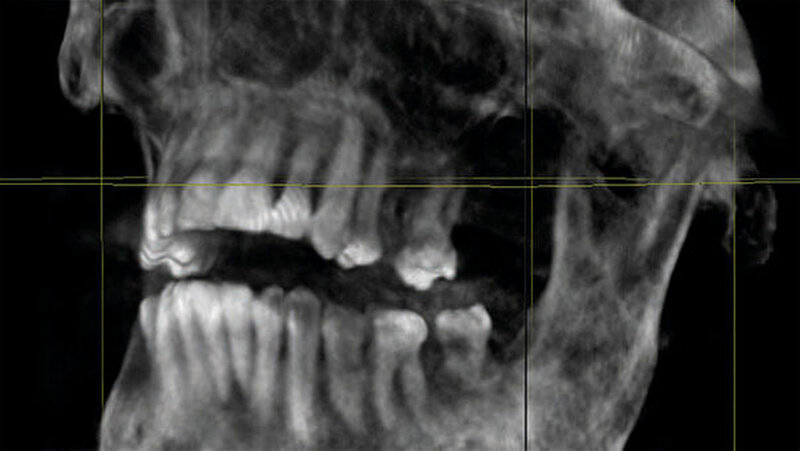

Zum Ausschluss einer Mittelgesichtsfraktur bei palpatorischem Weichteilemphysem erfolgte zur weiteren Diagnostik eine DVT-Aufnahme. Es zeigten sich keine Frakturen im Bereich des Mittelgesichts oder der Kiefer. Jedoch kam in der DVT-Bildgebung sowie der OPT-Optik ein massives Weichgewebeemphysem zur Darstellung (Abbildungen 2 bis 5).

Weiterhin wird deutlich, dass bei in aller Regel doch sehr eingeschränkter Beurteilbarkeit von Weichgewebe im DVT in diesem speziellen Fall eine weiterführende Diagnostik und Therapie eingeleitet werden konnte.

Das Emphysem war initial im DVT so eindrucksvoll sichtbar, dass es trotz fehlender klinischer Symptomatik im Thoraxbereich des Patienten, schwieriger Anamnese und blander zweidimensionaler Bildgebung der Lunge (RÖ-Thorax) der Faktor für eine weitere dreidimensionale Bildgebung (CT-Thorax) war, der letztendlich die Verdachtsdiagnose sicherte.

Zur Frakturdiagnostik im Mittelgesichtsbereich eignet sich das DVT sehr gut, außerdem ist die freie Luft des Emphysems im undifferenzierten Weichgewebe gut darstellbar.